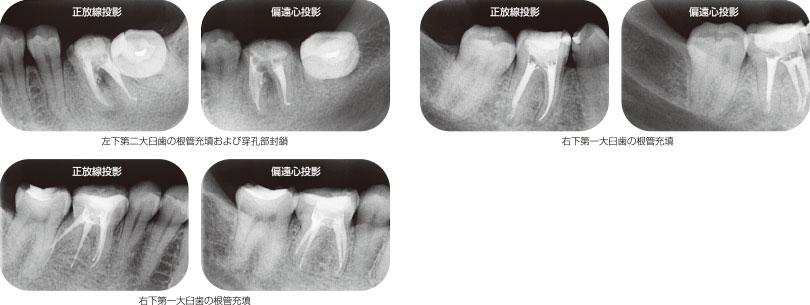

図19 ダイアペンとダイアガンによる根管充填。

ダイアペンとダイアガンを用いた根管充填を行うことにより、複雑な根管系にガッタパーチャをより緊密に充填することが可能となる(図19)。また従来の加熱軟化ガッタパーチャ根管充填法に比べると、根管充填材の到達度のコントロールも容易になる。

根管充填法により成績に差はでないと報告されているが、より確実な根管充填を従来の側方加圧根管充填法と同様もしくは短い時間で行え、しかも側方加圧根管充填でカバーできない根管にも充填することが可能となるのであれば、この方法をマスターするべきだと考えるのは筆者だけではないだろう。